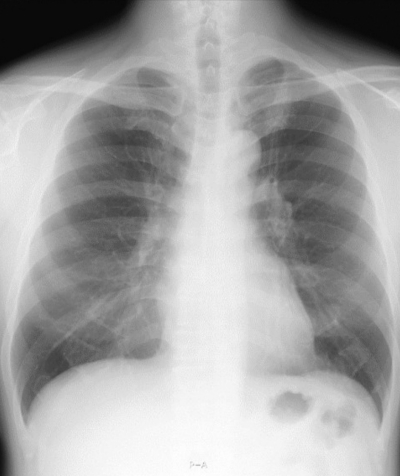

73歳の男性。健診で胸部エックス線写真の異常陰影を指摘されて受診した。65歳から高血圧症で内服治療中。喫煙歴は 20 本/日を 50 年間。気管支内視鏡下擦過細胞診で腺癌と診断された。FDG-PET では腫瘤に一致して集積を認める。他の部位には異常集積を認めない。胸部エックス線写真 正面及び胸部CTを別に示す。

治療方針を決定するために行うべき検査はどれか。